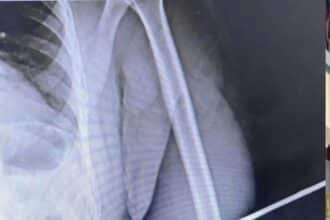

Ele deu entrada inicialmente no Hospital Geral de Roraima (HGR) com a flecha cravada no ombro esquerdo.

Após dar entrada na unidade hospitalar, o policial foi submetido a cirurgia para retirada da flecha.